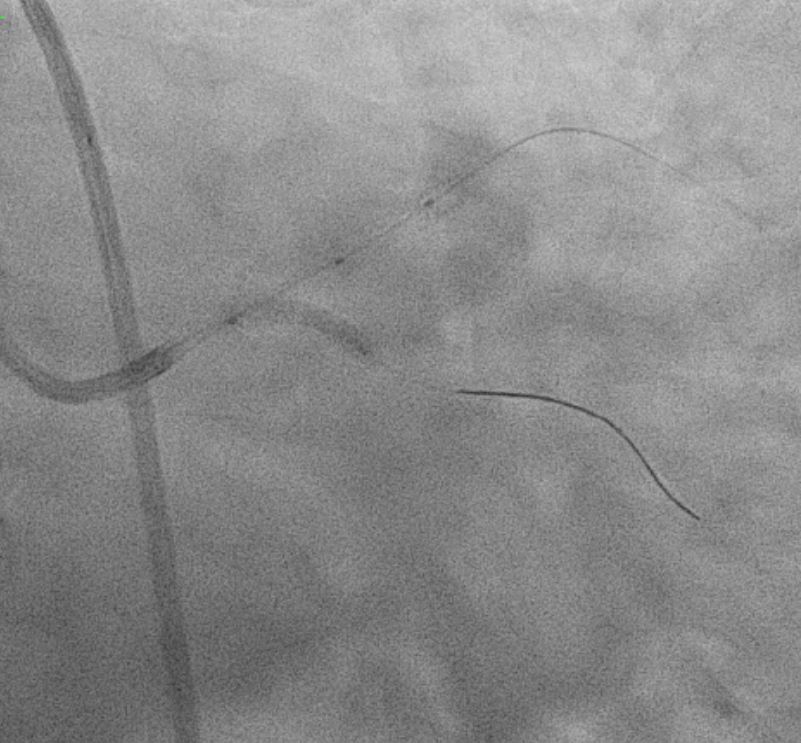

Right Radial approach, Slender 6/7Fr , EBU 3.5 7FR changedto EBU 3.0 7FR Sion blue to LCX, Run-through floppy to LAD IVUS run to LAD Fibro calcified lesion ostial LAD - calcium arc 180 degrees with calcium nodule, ostial LAD 3.48mm2 , tightest proximal LAD 2.31mm2 distallumen size 3.0mm and proximal 3.5mm and ostial 4.0mm ostial LM MLA 10.8mm Used microcatheter fine cross to LAD , Exchange with balloon trapping withRotaWireRotablator 1.5burr introduced- 2 runs high speed 180kph and2 runs at 80kph IVUS done post Rotablator - tightest proximal LAD 2.31mm2 -->3.22mm2 , ostial LAD 3.48mm2 -->4.51mm2 Predilate further NC 3.5x15mm up to 16atm Stented Synergy monorail 3.0x32mm body LM to proximal LAD at11atm with guide plus 6FRpost dilated NC 3.5x12mm up to 20atm Guiding catheter slipped out and lost the system, tried to reengage but challenging thus decided to change to right femoral puncture to use EBU3.5/7fr ,post dilate LM-LAD NC 4.0/12mm 6atmOstial LCX pinched - decided for Kissing balloon inflation and DCB LCX ostium predilated Ostial LCX 2.75x15mm up to 8atm Kissing inflation performed with NC emerge 3.5X15mm LAD, NC2.75x12mm in LCX 8atm DCB AGENT MONORAIL 2.75X15 MM 8atm 60seconds to ostial LCX last POT with NC 4.0x12mm up to 16atm IVUS done stent well opposed, Ostial LAD MSA 8.25mm2Proximal MSA 5.64mm2 TIMI III flow

In summary, this was a complex PCI for a severely fibro-calcified ostial and proximal LAD lesion with significant calcium arc and a calcium nodule confirmed on IVUS. Despite initial right radial access with a Slender 6/7 Fr system, guide support with EBU 3.5 and later EBU 3.0 remained suboptimal, ultimately necessitating conversion to a right femoral 7 Fr approach for adequate support. Overall, the case highlights the importance of adaptive access strategy, aggressive plaque modification, IVUS-guided optimization, and bifurcation management to achieve an excellent final physiological and angiographic result in a heavily calcified LM–LAD lesion.